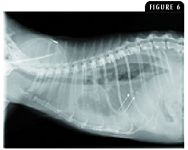

Clinical evidence of distant metastasis is a negative prognostic factor.12,26 Pulmonary metastasis is the most common cause of mammary-carcinoma–related deaths, and cats presenting with advanced lung involvement at diagnosis have a reported median survival time of only one month (Figure 6).8,16 The location of metastatic disease is a significant prognostic factor for both disease-free interval and median survival time, with cats with metastatic disease in regional lymph node, pulmonary, and pleural anatomic sites having a median survival time of 1,543, 332, and 188 days, respectively.43 In addition to the negative impact of distant metastasis, it has been anecdotally reported that cats with histologic evidence of lymphatic invasion have a median survival time of seven months compared with 18 months in cats without lymphatic invasion.50 Likewise in male cats with mammary carcinoma, lymphatic invasion is also a negative prognostic factor, with a median survival time of 195 days vs. 863 days in tumors positive or negative for lymphatic invasion, respectively.10

Figure 6. A lateral thoracic radiograph of a cat presenting for evaluation of dyspnea of one weeks duration. Past pertinent history included surgical resection of a mammary tumor nine months earlier. Radiographic findings are consistent with moderate to severe pleural fluid accumulation and multiple soft tissue metastatic lesions (white arrows).